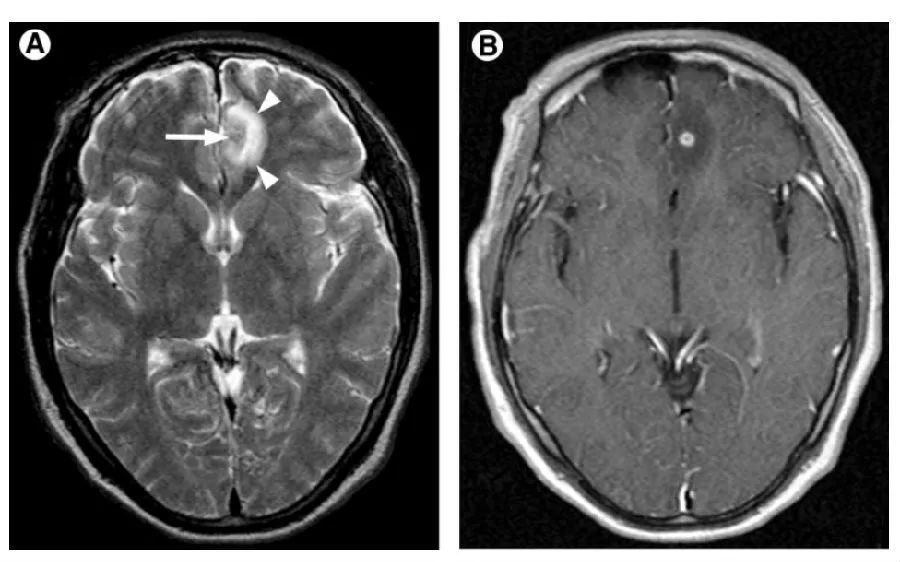

大脑里面「凹造型」:常见神经系统寄生虫感染影像表现

脑寄生虫病的影像诊断辅导二(20201126)